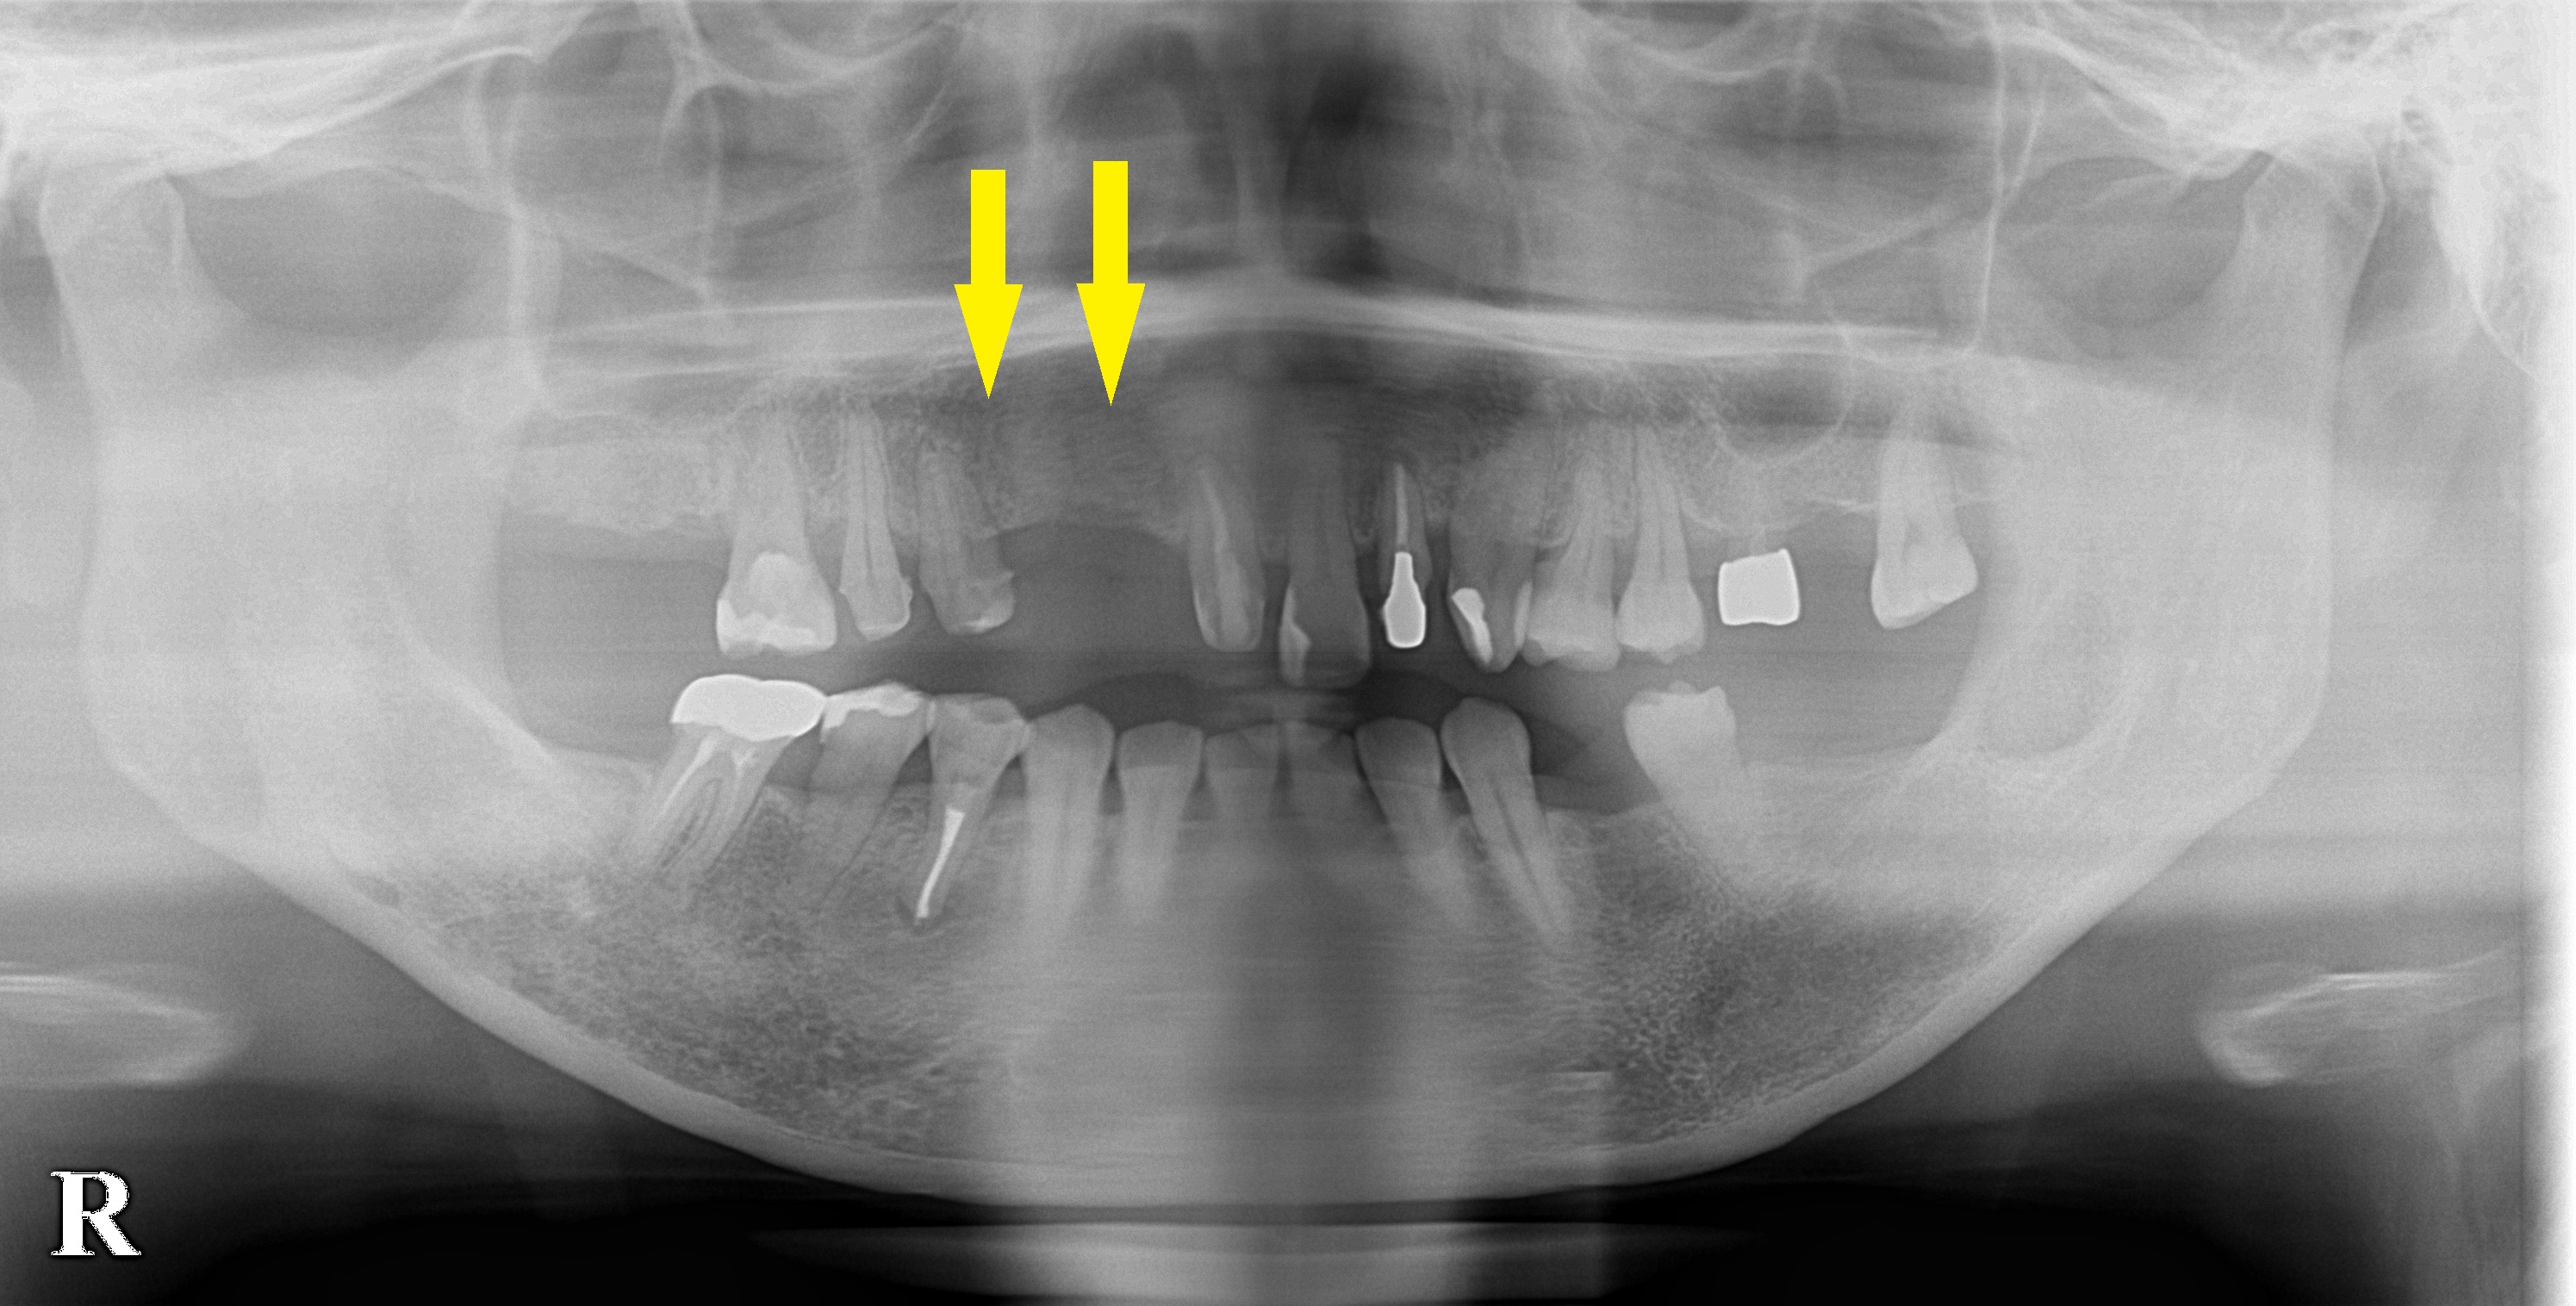

CTを撮ってみると、確かに、骨の幅がなく、通常のインプラント埋入は不可能でした。

下段左の写真が手術前のCTです。

骨がナイフのように尖って、薄いことが分かります。